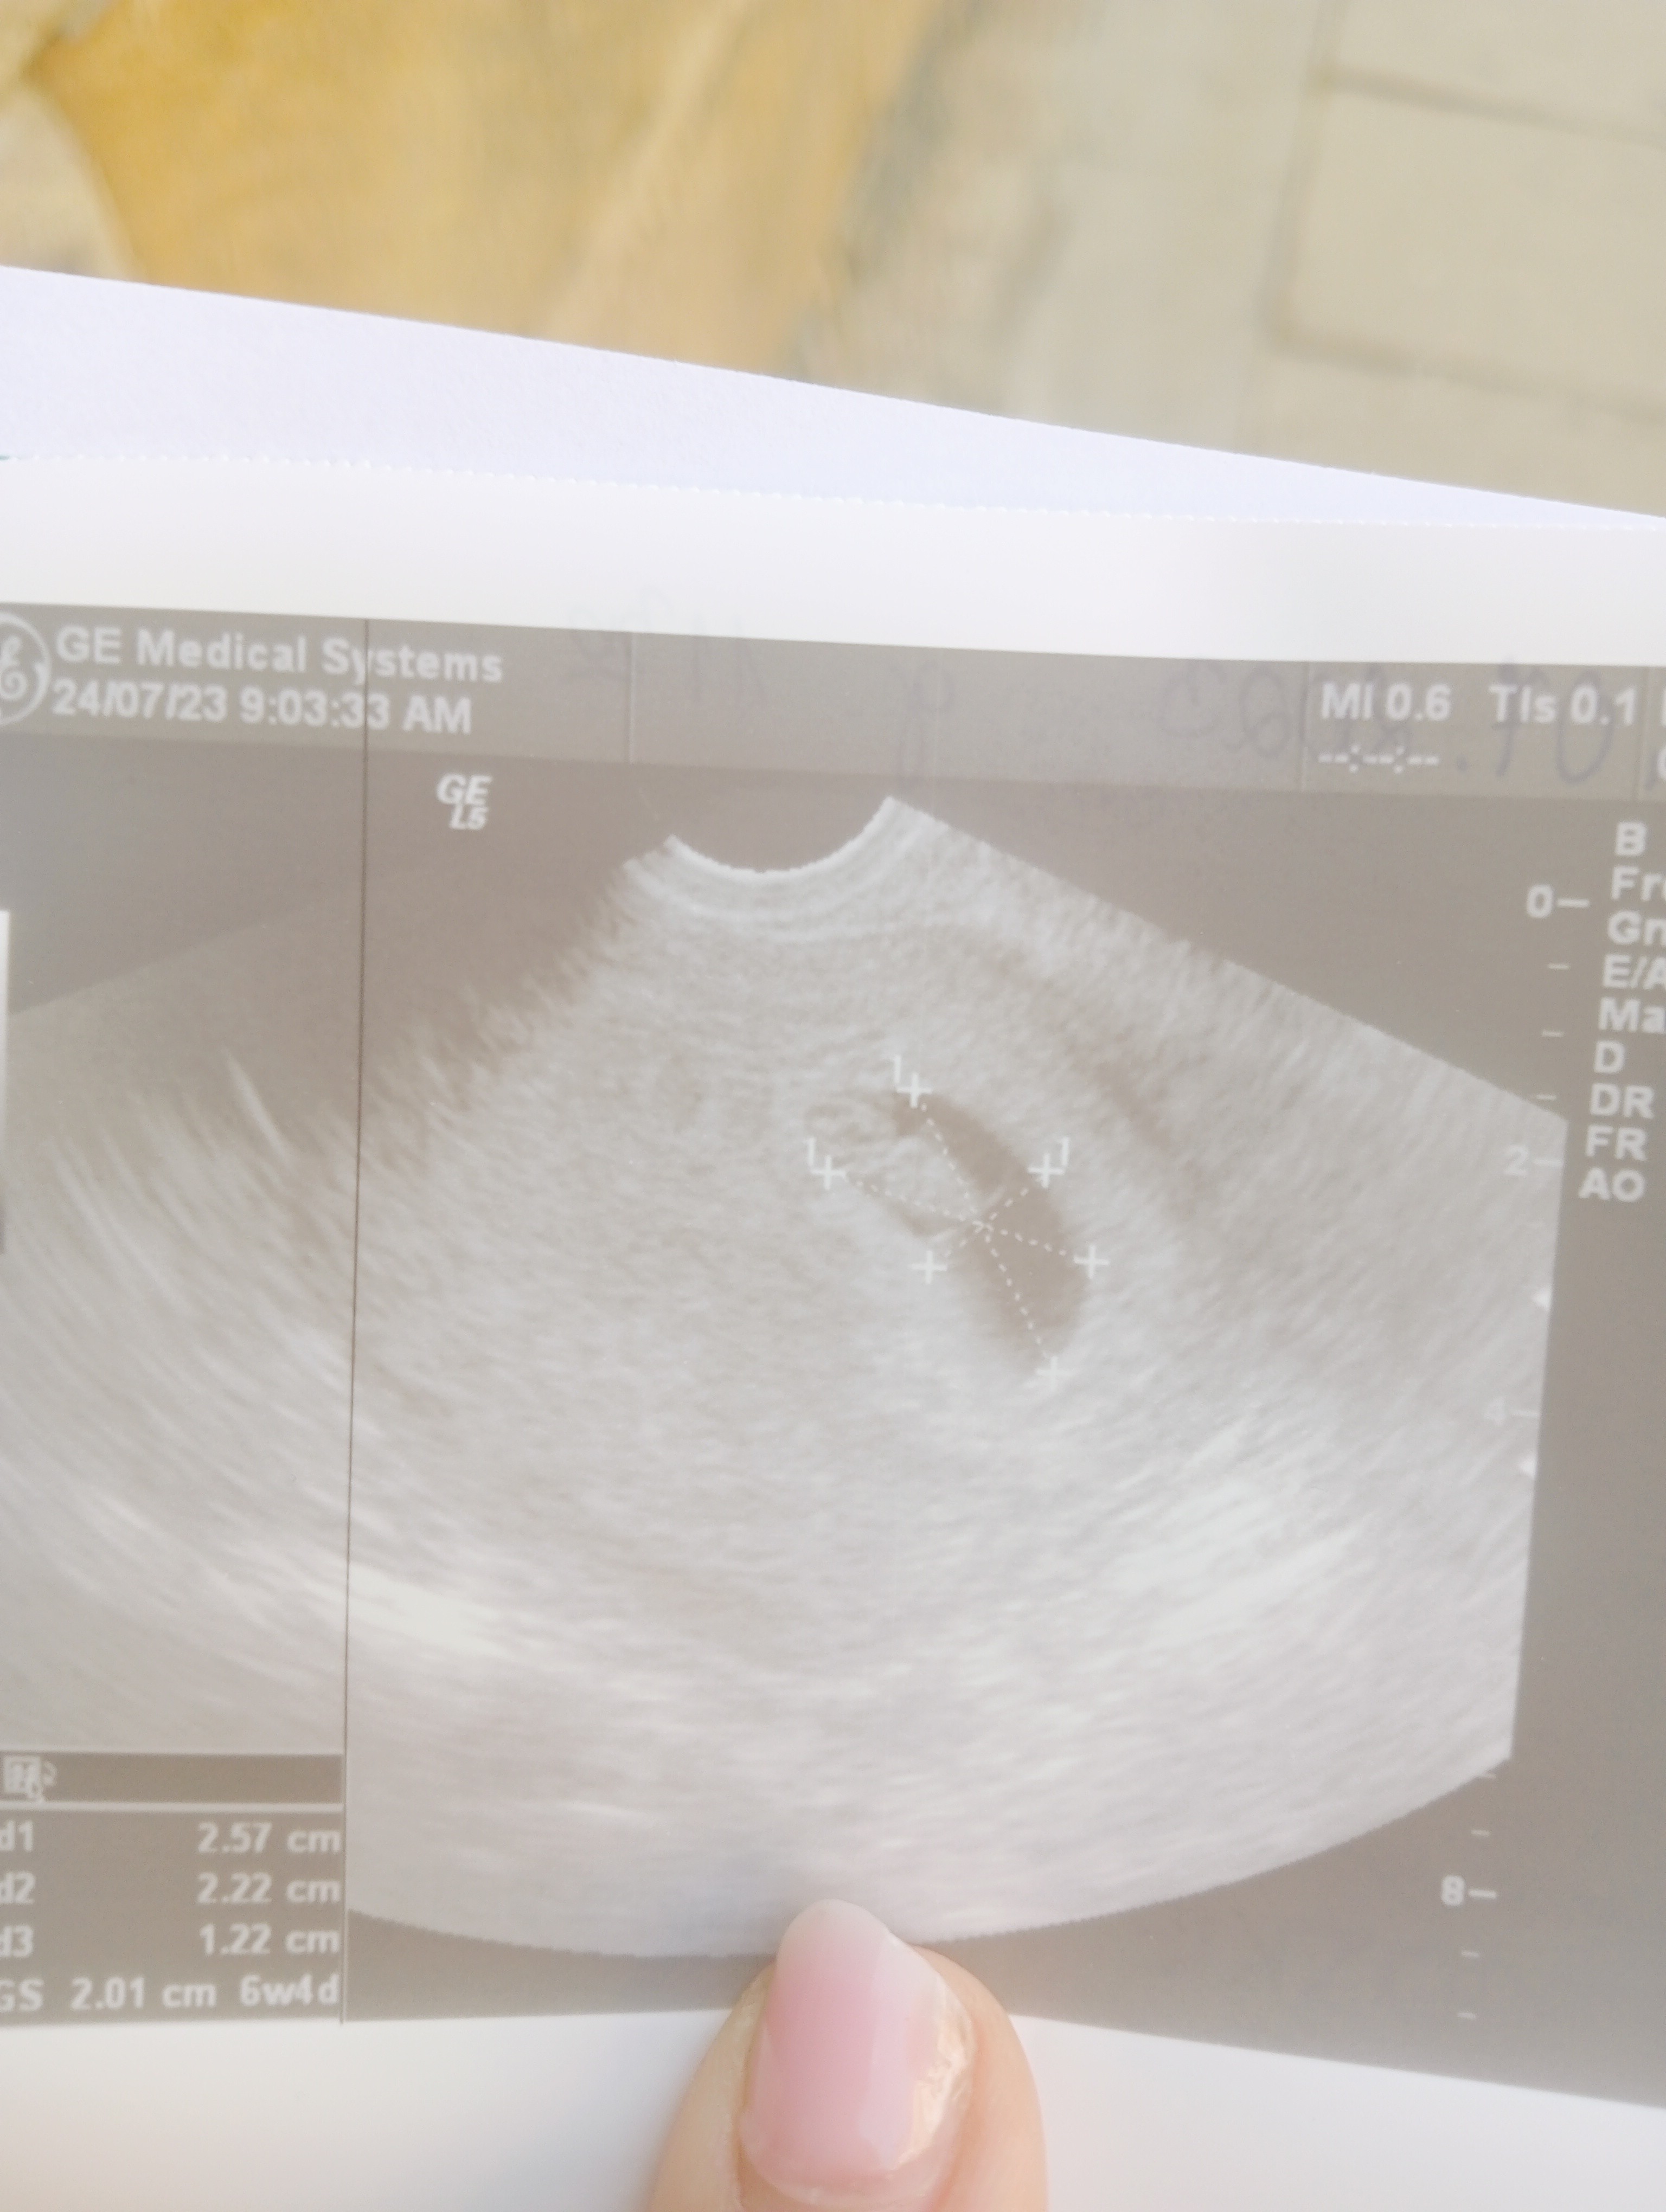

Hej 🙂 ostatnią owulację miałam 29 Czerwca.

BHCG:

12.07 - 54,95

14.07 - 117,25

18.07 - 480

Powiedzcie czy to nie jest za mały przyrost?

Jak narazie wszystko ok. Ciąża dużo młodszą niż z om

Załączniki

• IMG20230724084614.jpg